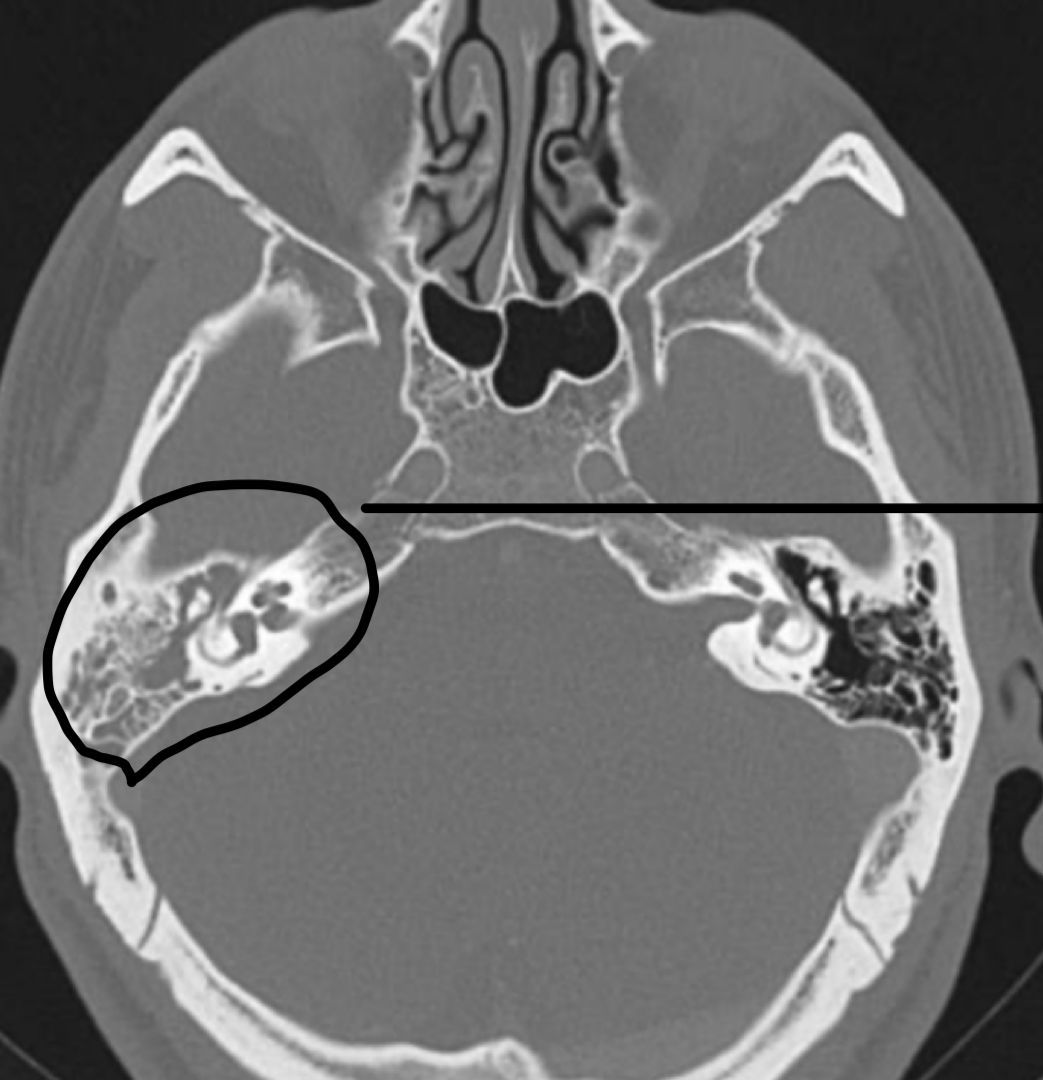

¿Cuáles son las pistas diagnósticas en la TC de la otitis media?

¿Cuáles son los hallazgos radiológicos en la TC de mastoiditis?

¿Cuál es una pista característica del colesteatoma?

Destruye hueso